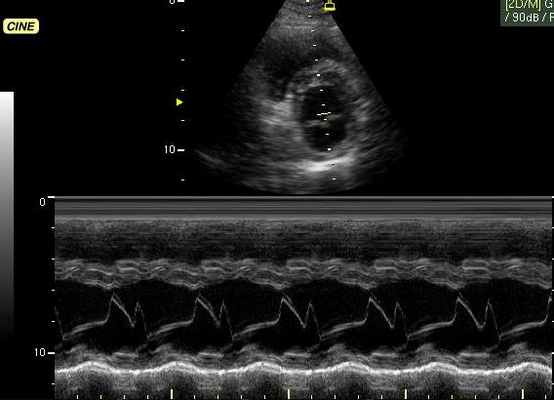

M-режим (M – motion) – режим одномерного сканирования с получением развертки в реальном масштабе времени, который применяется для регистрации пространственного положения исследуемых объектов во времени (отслеживания движения исследуемых структур). Наиболее часто данный режим используется при кардиологических исследованиях совместно с B-режимом, где B-режим используют для навигации.

- М-режим (M-mode). Это «усеченный» вариант предыдущего, при котором используется для анализа только одномерное изображение. Основное внимание уделяется одной из линий 2D трассировки, что позволяет более детально исследовать движения створок клапанов и сердечной мышцы.